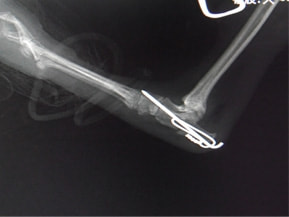

症例3:キルシュナーワイヤーのピンニングによる整復

ペルシャ猫 11ヶ月齢 雄

他院にて左大腿骨遠位の成長板骨折(salter-harrisⅠ型)が認められており、治療相談を目的として来院。当院にて、キルシュナーワイヤーを用いたピンニングにより骨折部位の整復を行いました。術後の経過は良好で、現在も経過観察中です。

術前レントゲン

術後レントゲン

機器

Arthrex社のターゲティングデバイスを用いてピンニングの位置を調整することで、確実な固定を行っています。当院ではこの手術器具以外にも、人の手術にも使用される様々な器具を導入し、手術精度を高め、また医療メーカーと新しい器具の開発、試作にも取り組んでおります。